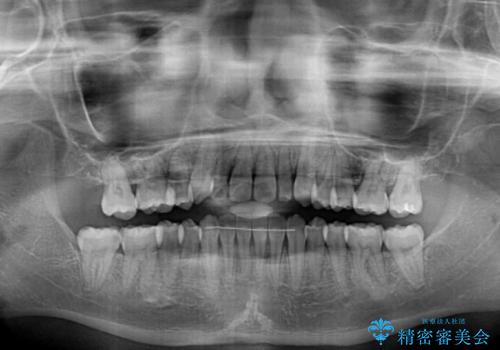

- 上顎の重なっている前歯を気にして来院された患者様です。

重なっている部分は抜歯が必要で、歯の移動量が多く、更には右側にずれている正中を改善する必要がありました。

インビザライン単体での治療は困難と判断し、補助装置により八重歯移動後にインビザラインを用いることとしました。

非常にしっかりとマウスピースを装着してくださいましたが、前歯の排列がなかなか仕上がらずに期間がかかってしまいました。